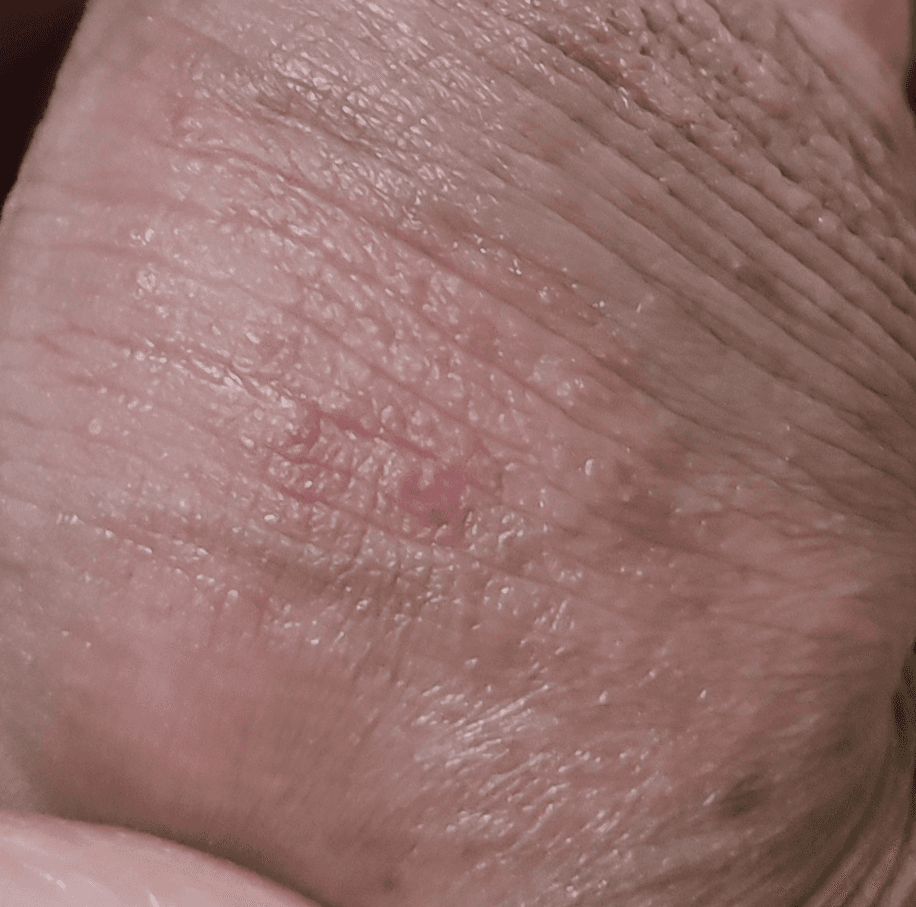

노포경 상태의 남자입니다. 요도염 중상 후에 귀두 앞 부분이 부풀어 오른 후에 귀두 입구와 닿아있는 표피에서 발진이 일어났습니다.

발진이 일어나긴 했는데 가렵지는 않고 하루에 한 두 번정도 따끔거리는 증상이 일어나긴 하는데~

이 것이 헤르페스인지 아니면 다른 병변인지 궁금합니다.

마지막 성관계는 2월 17일입니다.

• 2번 째 사진

사진의 소견을 통해서 헤르패스가 강력하게 의심되거나 하진 않으며 염증 소견이 보이긴 합니다. 관련하여서는 방치를 하거나 하지 마시고 비뇨의학과에 다니면서 치료를 하시는 것이 안전하겠습니다.